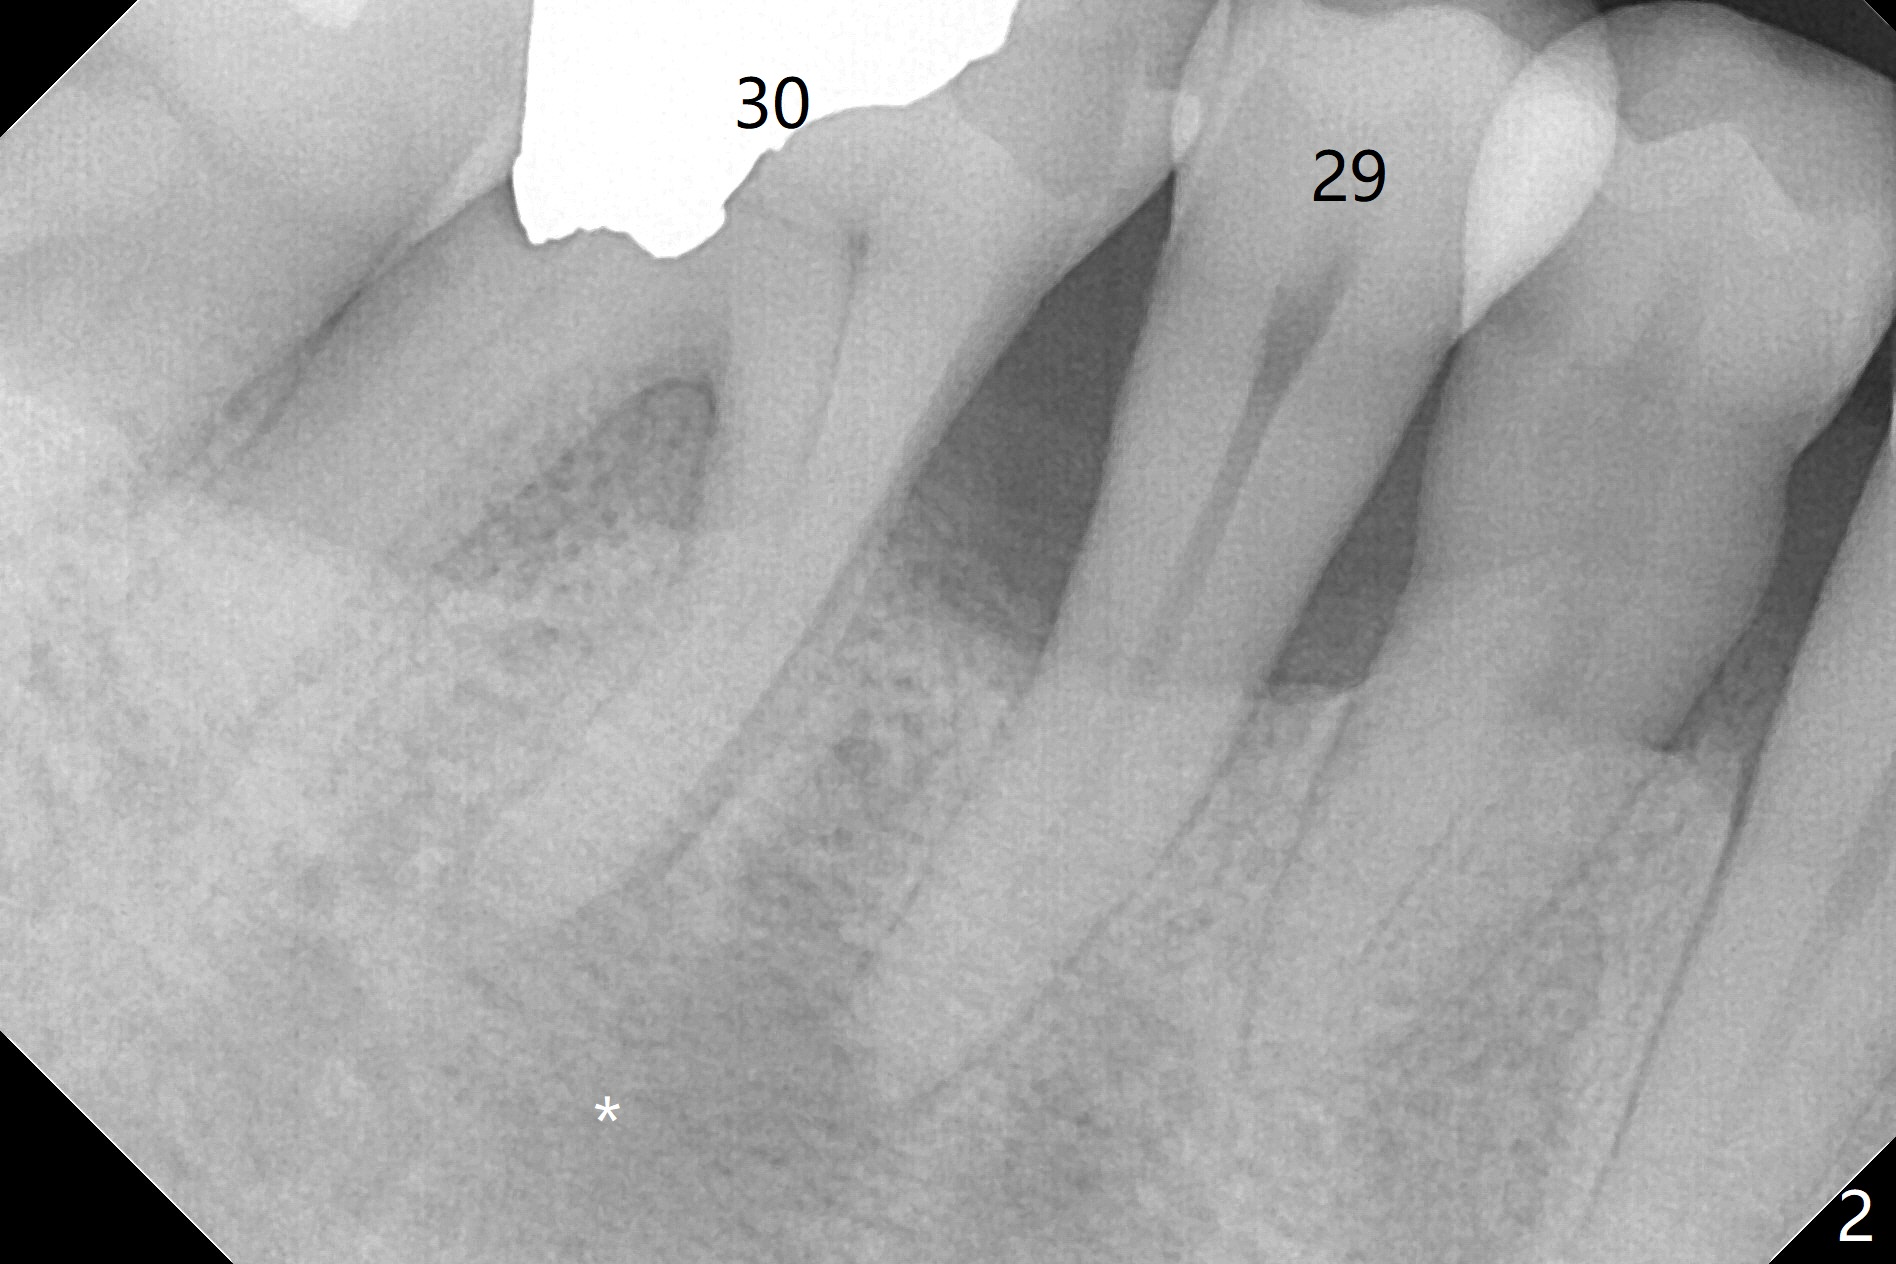

A 60-year-old man (smoker, 1/3 to 1/2 ppd) with large DO amalgam at #30 develops pain and mild swelling apparently apical to #29 (Fig.1-3). Both teeth (having fused PARL (periapical radiolucency) *) have mild percussion with the tooth #29 having higher mobility. CBCT shows apical defect (Fig.3 >). Three weeks earlier, the tooth #19 had much more severe infection with a similar apical defect (Fig.4 >). Combined with history of repeated infection associated with #30, the tooth is extracted with difficulty in obtain sound anesthesia. Socket preservation is performed instead of immediate implant (Fig.5 (*: Vanilla Graft)). CBCT makes it easy to diagnose 2 canals at #28 (Fig.6 as compared to Fig.2). Pain gradually decreases 3 days postop. In fact he has hypertension and smokes.